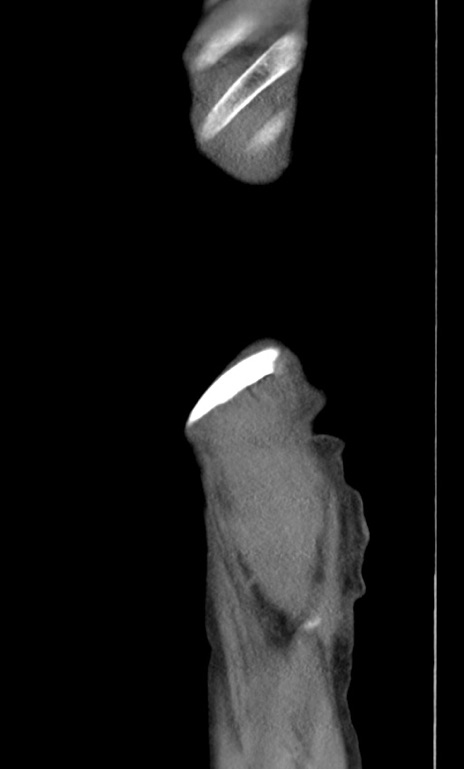

横断像

【症例】 70歳代男性

【主訴】右鼠径部腫瘤、疼痛

【現病歴】本日朝より上記主訴あり、受診。

【既往歴】膀胱癌にて膀胱全摘、両側尿管皮膚瘻

【データ】WBC 5600、CRP 0.56